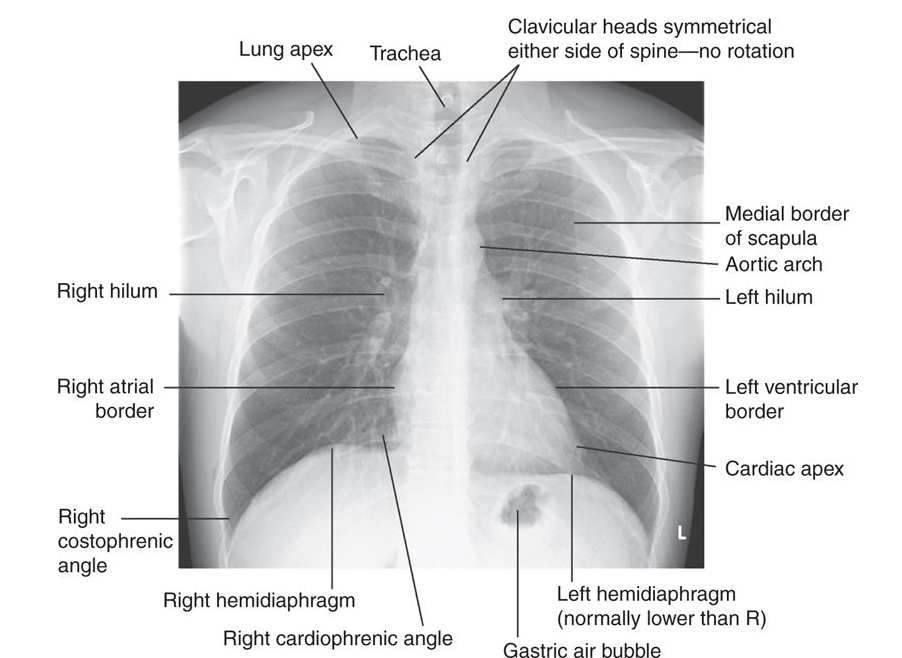

The ‘plain’ chest X-ray

This is performed on the majority of patients suspected of having chest disease. A postero-anterior (PA) film provides information on the lung fields, heart, mediastinum, vascular structures and the thoracic cage (Fig. I) above. Additional information may be obtained from a lateral film, particularly if pathology is suspected behind the heart shadow or deep in the diaphragmatic sulci. An approach to interpreting the chest X-ray is given in Table A, and common abnormalities in Table B.

Table A : How to interpret a chest X-ray

| Name, date, orientation | Films are postero-anterior (PA) unless marked |

| AP to denote antero-posterior | |

| Lung fields | Equal translucency? |

| Check horizontal fissure from right hilum to sixth rib at the anterior axillary line | |

| Masses? Consolidation? Cavitation? | |

| Lung apices | Check behind the clavicles |

| Trachea | Central? (Midway between the clavicular heads) |

| Paratracheal mass? Goitre? | |

| Heart | Normal shape? |

| Cardiothoracic ratio (should be < half the intrathoracic diameter) | |

| Retrocardiac mass? | |

| Hila | Left should be higher than right |

| Shape? (Should be concave laterally; if convex, consider mass or lymphadenopathy) | |

| Density? | |

| Diaphragms | Right should be higher than left |

| Hyperinflation? No more than 10 ribs should be visible posteriorly above the diaphragm) | |

| Costophrenic angles | Acute and well-defined? (Pleural fluid or thickening, if not) |

| Soft tissues | Breast shadows in females |

| Chest wall for masses or subcutaneous emphysema | |

| Bones | Ribs, vertebrae, scapulae and clavicles |

| Any fracture visible at bone margins or lucencies? |